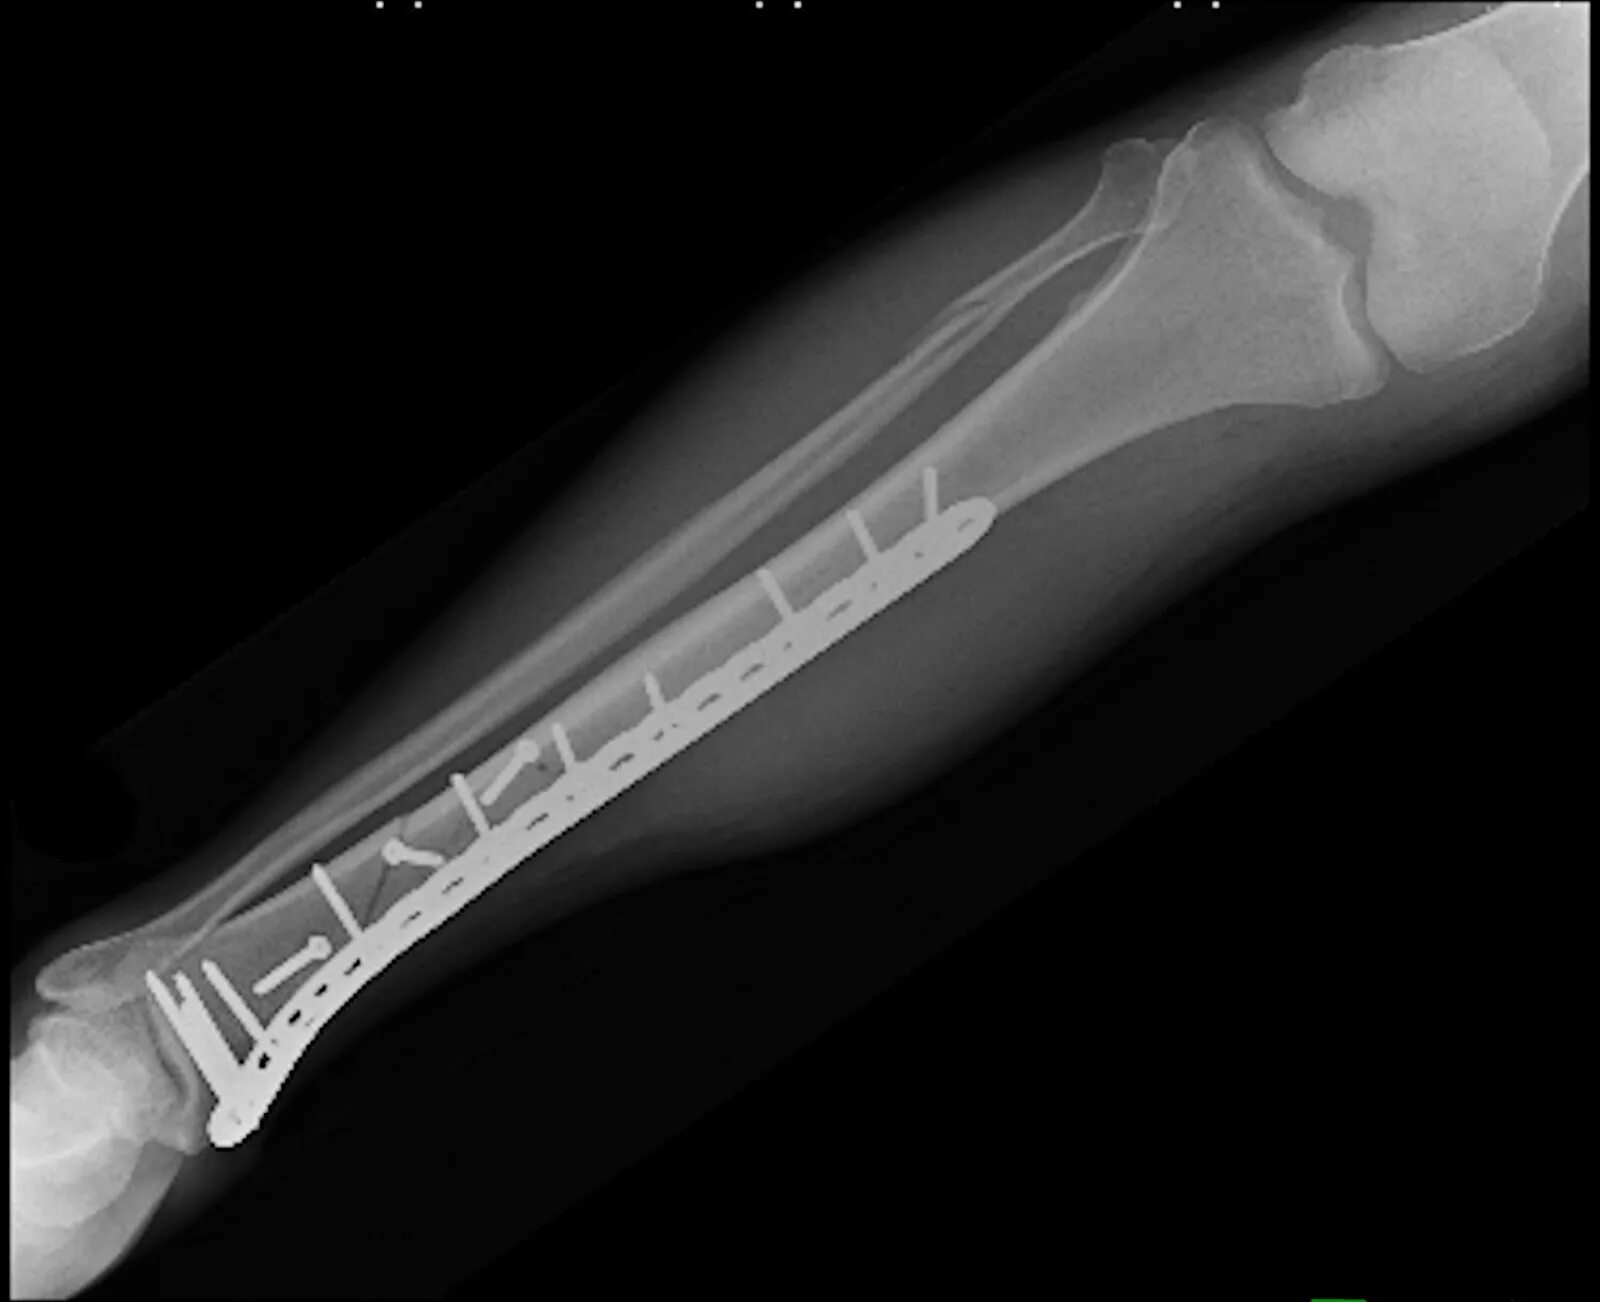

A fracture is a broken bone